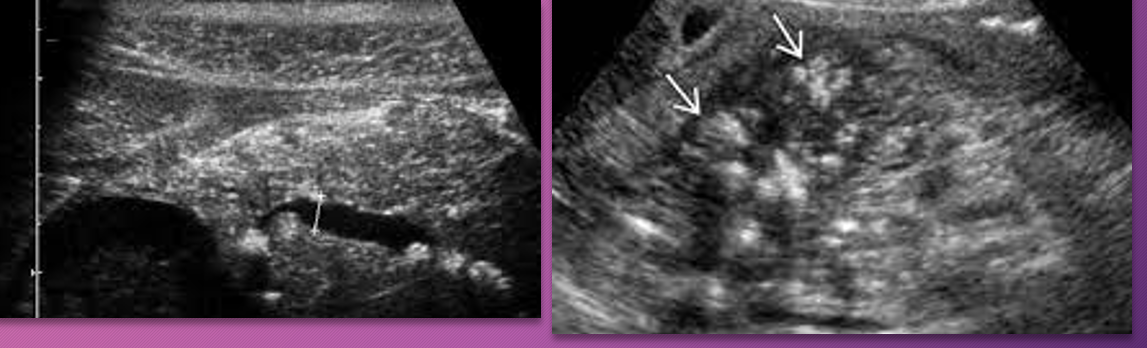

Sonographically, chronic pancreatitis may appear _____ or ______ with increased ______, size _____, ______ borders, and ______ duct

localized; diffuse; echogenicity; reduced; irregular; dilated

What is a classic finding of chronic pancreatits?

Calcification

Normal Pancreatic duct measurement:

Head: ___-____ mm

Body: ___-____ mm

Tail: ___-___ mm

3-3.5; 2-2.5; 1.5-2